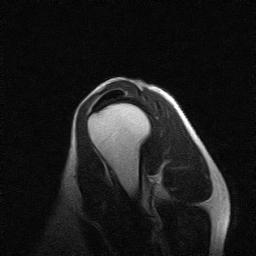

| Numero della serie: | 6 | Descrizione della serie: | FS T2 SAG |